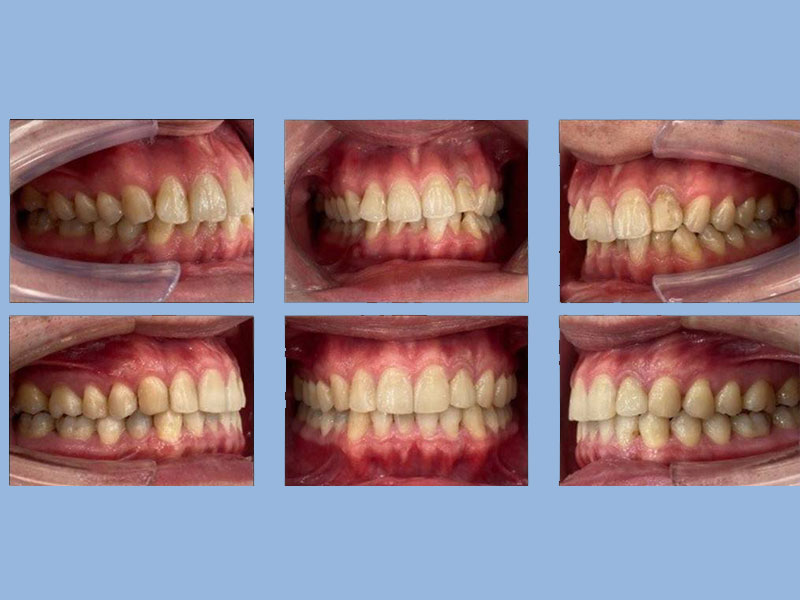

許先生 (24歲) 矯正完成

狀態 : 牙齒擠、暴牙、沒拔牙